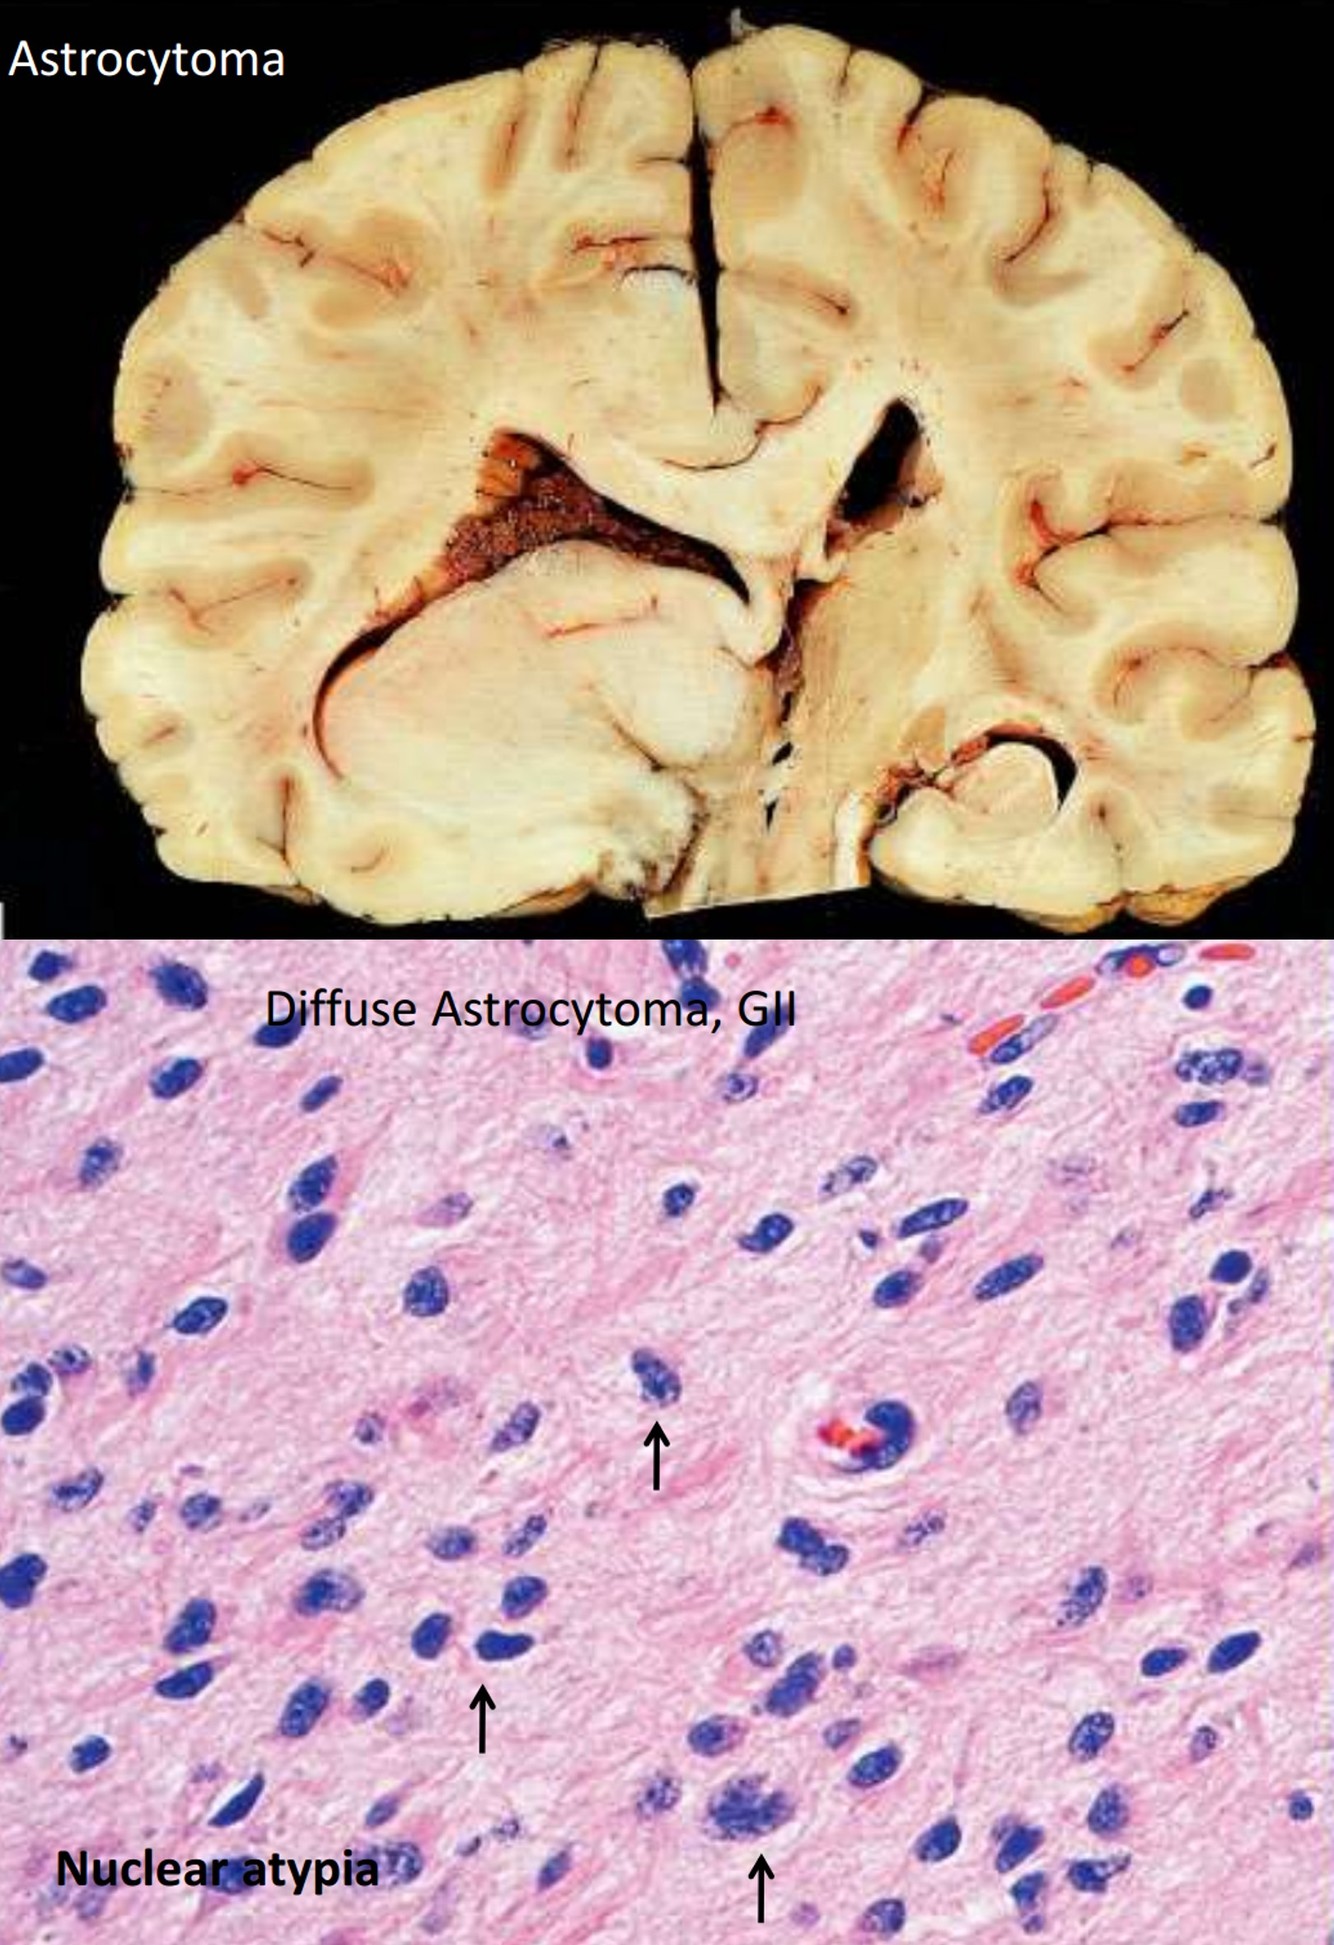

- Diffuse astrocytoma

Infiltrating Astrocytoma

Infiltrating Astrocytoma

- 80% of primary adult tumors

- WHO Grade II: diffuse astrocytoma

- Diffuse astrocytoma: 35 y/o